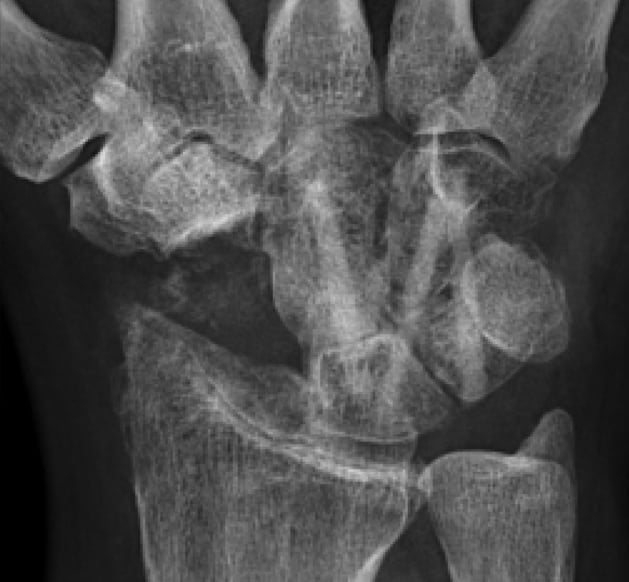

6 Wochen postoperativ

Röntgenbild bei Gipsabnahme. Der beginnende Durchbau ist noch nicht sicher zu erkennen.